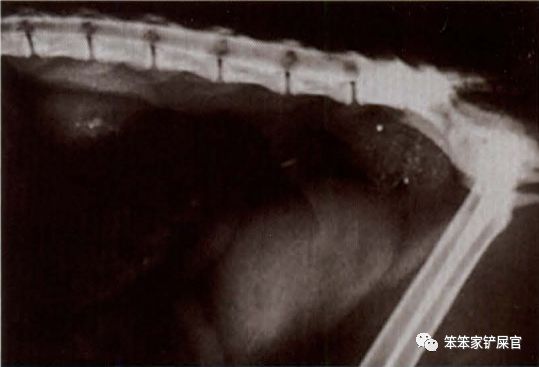

- X光照影、脊髓造影、核磁共振:检查脊髓是否有异常,确定脊髓是否有受到压迫或是否有脊髓囊的出现。